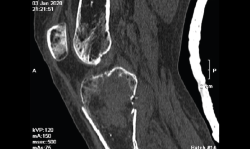

Tomografía axial computarizada

Es un método de diagnóstico médico que permite observar el interior del cuerpo humano, a través de cortes milimétricos transversales al eje cefalocaudal, mediante la utilización de los rayos X(9).

Los equipos modernos (TAC helicoidal o multicorte) permiten obtener imágenes volumétricas isotrópicas, lo que significa que la reconstrucción multiplanar en cada uno de los ejes tiene la misma resolución. Además, permite hacer reconstrucciones tridimensionales.

Entre las ventajas de la TAC, cabe destacar que permite obtener imágenes de hasta 1 mm y que, debido a la amplia gama de tonos grises que maneja, permite identificar con precisión los diferentes tejidos estudiados.

1. Fracturas

Es esencialmente útil en la valoración de los trazos de fractura, de su extensión, del escalón intraarticular y el desplazamiento. También es importante en la planificación del tratamiento de las fracturas intraarticulares complejas.

Los nuevos equipos, con múltiples detectores, permiten realizar cortes finos (submilimétricos) y reconstrucciones en cualquier plano del espacio o tridimensionales (3D) de gran calidad, que facilitan la valoración de estas lesiones(7).

2.4. Consolidación viciosa

Se produce cuando los fragmentos consolidan en mala posición, con deformidades que alteran el eje del miembro inferior (Figura 24).

Figura 24. Corte de reconstrucción sagital y coronal de tomografía axial computarizada de rodilla: consolidación viciosa de la epífisis tibial proximal.